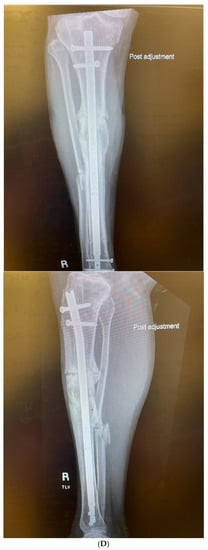

3.4. Case 4-Infected Malunion-Nonunion Femur Correction: True Dome Osteotomy

A young adult male presented new-onset diabetic ketoacidosis and sepsis. The study revealed a large thigh abscess circumferentially surrounding the left femur (Figure 9A). No other source was identified during workup. The patient underwent multiple debridements, and initially, a cortical window was made for the egress of intramedullary purulence. Subsequent debridements revealed extensive osteomyelitis. During debridement with intramedullary antibiotic nailing, the femur fractured and was eventually resected to attain source control (Figure 9B). A 13-cm segmental defect was stabilized using an antibiotic-coated locked nail with the surrounding antibiotic bone cement spacer Figure 9C). The CORA analysis revealed a five-degree varus deformity and no significant sagittal plane deformity. After source control with intravenous antibiotics and a 3-month course of oral antibiotics, the workup, including a biopsy and culture, resulted in no growth and no sign of ongoing infection. A bifocal true dome osteotomy with intercalary cortical allograft was chosen based upon a low likelihood of compliance with bone transport. A standard lateral approach elevating the vastus lateralus was used to access the femur. Reverse reamers and standard acetabular reamers were used for mating the bone surfaces (Figure 9D). The varus alignment was addressed using a blocking screw as the nail was passed; no gap was produced at the osteotomy due to its true dome shape. The dome osteotomy interfaces were autografted and compressed with a magnetic motorized nail, with additional compression at the subsequent outpatient visits (Figure 9E). The patient had soft tissue and allograft interface healing without incident and returned to gainful employment (Figure 9F).

Figure 9.

(A) A young adult male presented new-onset diabetic ketoacidosis with sepsis. He was found to have a large spontaneous left thigh abscess, as seen on CT imaging. (B) Multiple surgeries resulted in a femur fracture and subsequent segmental resection of approximately 13 cm of the patient’s femoral diaphysis. (C) The patient eventually attained source control with resection, antibiotic spacer, and an antibiotic coated nail. Patient has a 5-degree distal varus deformity. (D) The patient underwent a true dome osteotomy of the proximal and distal ends of the allograft/host bone interfaces. Fresh frozen allograft preparation using a reverse reamer is shown prior to implantation. (E) Motorized compression of the construct was employed with early and subsequent compression. Four-month follow-up showed restored neutral alignment, incorporation/interface healing of the dome osteotomy sites, bone regenerate across the interfaces, normal lab markers, and return to gainful employment. (F) Twelve-month follow-up continued to demonstrate interface healing without infection recurrence.